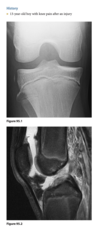

An 18-year-old man with acute injury of the right knee

Sagittal proton-density (Fig. 2.14.1)

and fast spin-echo, T2-weighted fat-suppressed

(Fig. 2.14.2) MR images show an area of increased

signal intensity within the anterior cruciate ligament

(ACL), the so-called pseudo-mass (arrows); nonvisual-

ization of the normal ACL fibers; and a joint effusion.

A sagittal fast spin-echo, T2-weighted fat-suppressed

MR image through the lateral joint compartment

(Fig. 2.14.3) shows high-signal-intensity areas in the

subchondral regions of the midportion of the lateral femoral condyle and the posterolateral tibial plateau,

the so-called “kissing contusions”

Full thickness tear of the ACL

Conventional radiographic findings of an ACL

tear include avulsion fractures from the femoral or

tibial attachment of the ACL (Fig. 2.14.4, arrow), the

Segond fracture (Fig. 2.14.4, arrowhead), or a deep

lateral sulcus sign (Fig. 2.14.5, arrow).

MRI features of the torn ACL include an irregular

or wavy contour with decreased angulation on the

sagittal images (i.e., “lying down” or vertically ori-

ented ACL), increased signal intensity on all MRI

sequences in the region of the ACL (i.e., so-called

“pseudo-mass”), posterior displacement of the lateral

meniscus (i.e., “uncovered lateral meniscus” sign),

loss of the normal obtuse curvature with increased

angulation of the posterior cruciate ligament, undu-

lation of the patellar tendon, and the “empty notch”

sign, which is also seen on arthroscopy.

Bone

impaction from transient subluxation results in

the characteristic osseous contusions involving the posterolateral tibial plateau and midportion of the

lateral femoral condyle (i.e., “kissing contusions”).